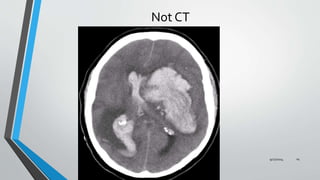

Not CT

EXCLUSION CRITERIA

Intraventricular haemorrhage of any sort.